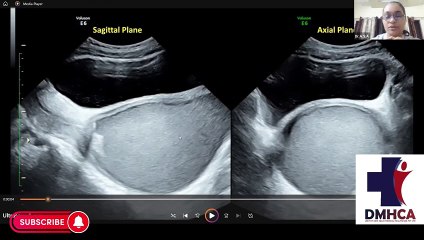

IMA eVarsity offers continues medical cources by an accredited CME provider in diploma in family medicine,fellowship in diabetes mellitus and other post graduate medical cources.